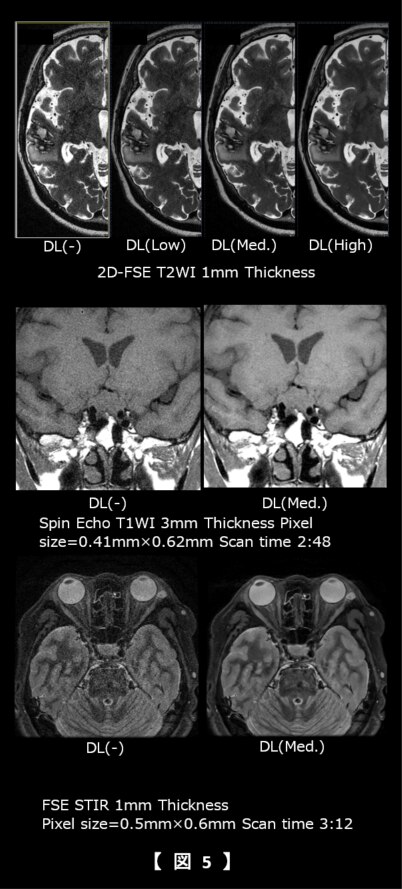

頭部領域では、脳や眼窩領域の従来より薄いスライス厚を臨床上現実的な撮像時間で、下垂体領域では従来より高SNRで収集することが可能となり(図5)、整形領域ではオフセンターの高SNR・高分解能画像に加え、低SNRのDWIにおいてもSNRを向上させることで診断能の向上に寄与していると考えられる(図6中段)。また腹部の膵管領域においても高空間分解能に撮像することが可能となった。さらにBWを広帯域化することでケミカルシフトの低減と高空間分解能かつ高SNR画像の両立が期待できる(図6下段)。